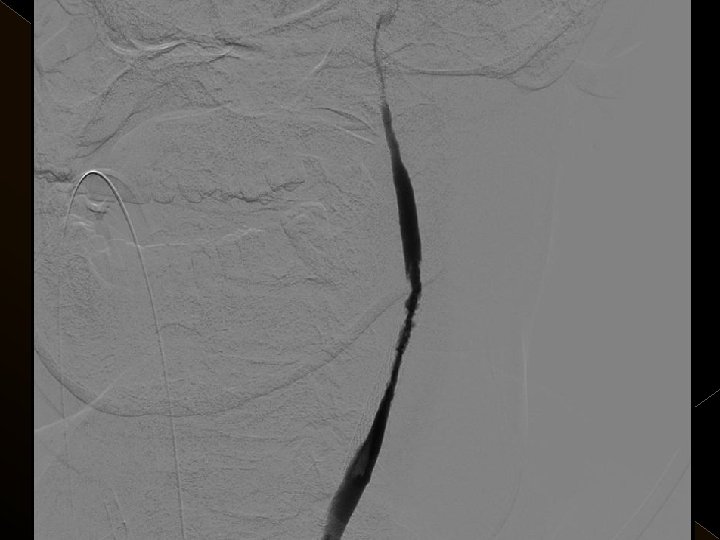

KOMPLİKASYONLAR Ponksiyon bölgesi komplikasyonları � Trombektomi stentine ait komplikasyon (*1) � Diseksiyon(*2) � Karotikokavernöz fistül (‘ 1) � Hemorajik komplikasyonlar(‘ 5) Semptomatik-nonsemptomatik � İskemik komplikasyonlar (3) � Reoklüzyon (2 i. a) � Kontrast madde nefropatisi �